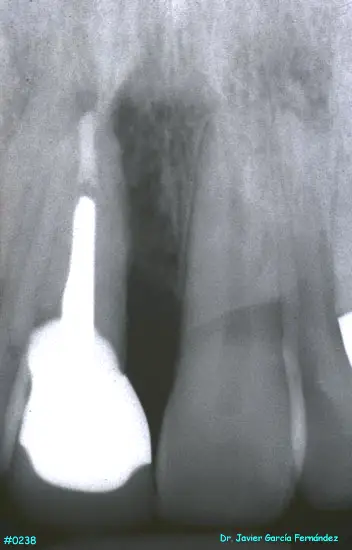

ATLAS DE CIRUGIA PERIODONTAL